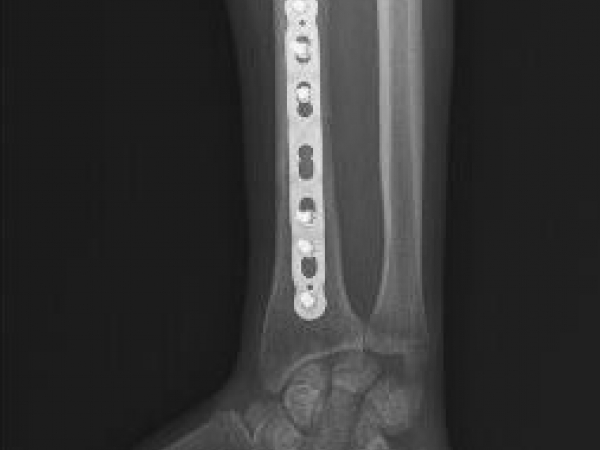

TRUE LOCK 3.5mm Ulna Radius Plate

TRUE LOCK 3.5mm Ulna Radius Plates are indicated for fractures of ulna, radius and fibula shaft.

Images Gallery